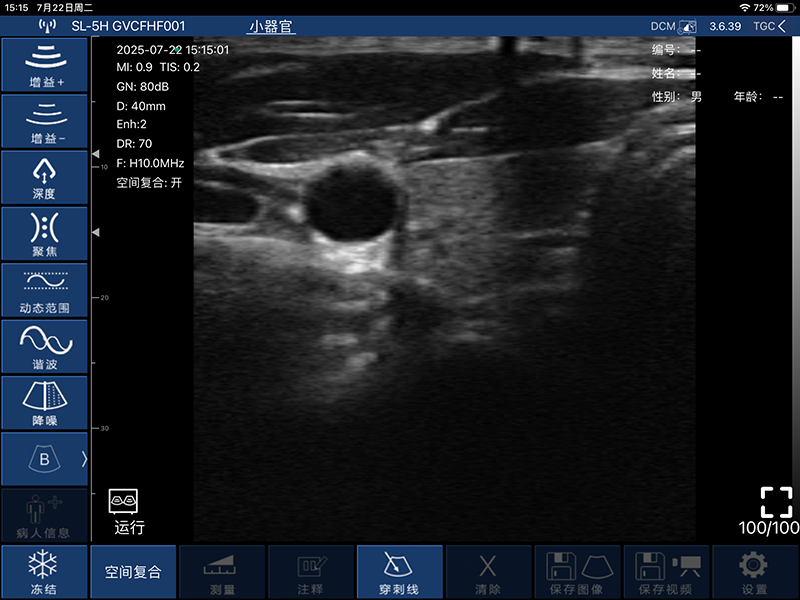

带指套探头的掌上彩超,小小的掌超主机放在口袋可随处走,手指套着探头即可完成打图成像,让手不再需要握着探头而可解放出来还能拿其他东西,特别适合术中等应用

- 穿刺辅助功能:平面内穿刺引导线功能,平面外穿刺引导与血管自动测量功能

- B模式